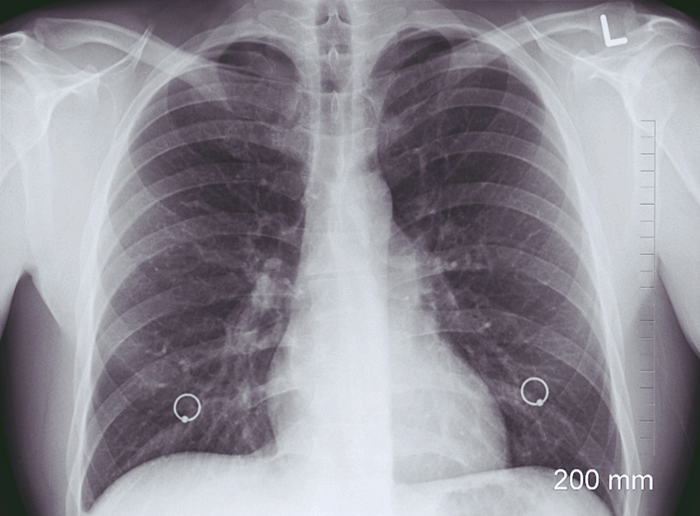

- 흉부 X-ray:

- 양쪽 폐에 미세한 석회화 결절이 광범위하게 분포된 특징적인 소견이 보임.